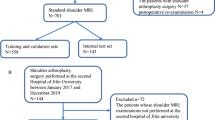

The algorithm was developed using 6793 shoulder radiograph series performed between January 2015 and June 2018, which were labeled based on ultrasound or MRI conducted within 90 days, and clinical information (age, sex, dominant side, history of trauma, degree of pain). The output was the probability of significant rotator cuff tear (supraspinatus/infraspinatus complex tear with > 50% of tendon thickness). An operating point corresponding to sensitivity of 98% was set to achieve high negative predictive value (NPV) and low negative likelihood ratio (LR−). The performance of the algorithm was tested with 1095 radiograph series performed between July and December 2018. Subgroup analysis using Fisher’s exact test was performed to identify factors (clinical information, radiography vendor, advanced imaging modality) associated with negative test results and NPV.